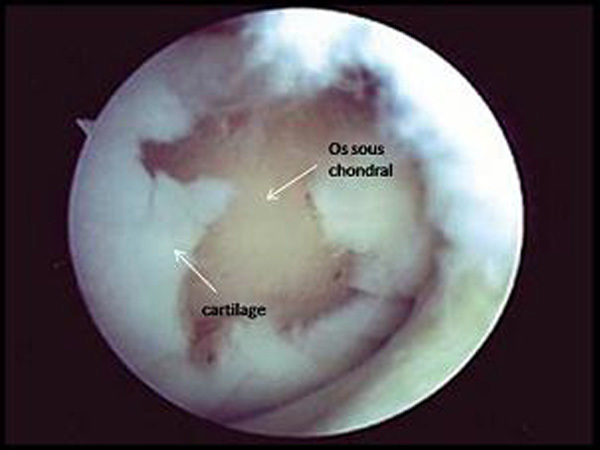

Vue arthrosique d’une lésion chondrale profonde. Les pertes de substance chondrale profonde ne se réparent pas spontanément ou sont, en cas d’atteinte associée de l’os sous-chondral, remplacées par du tissu fibrocartilagineux non fonctionnel à partir des cellules souches médullaires. Cela pose un problème considérable chez le sujet jeune, car ces lésions non seulement entraînent des douleurs et une invalidité mais sont génératrices d’arthrose précoce et parfois sévère.